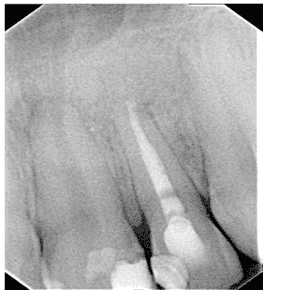

After three months using the obturator prosthesis, new control tests were performed, and immediate surgical intervention was necessary, because the neoplastic lesion had recurs (figure 22). On the patient’s return, after the first surgery (figure 23) and with the result of the histopathological examination (Appendix 3), which indicated margin involvement. The medical team intervened and elaborated another treatment plan, which consisted of surgical removal with margin enlargement. In a new dental visit, twelve days after the second surgery (figure 24), the histopathological examination again indicated compromised margins (Appendix 4). Therefore, a more invasive surgery was planned by the medical team, which may lead to facial involvement.

Figure 22: Recurrence of the lesion.

Figure 23: Surgical step 1 of removal.

Figure 24: Surgical step 2 of removal.